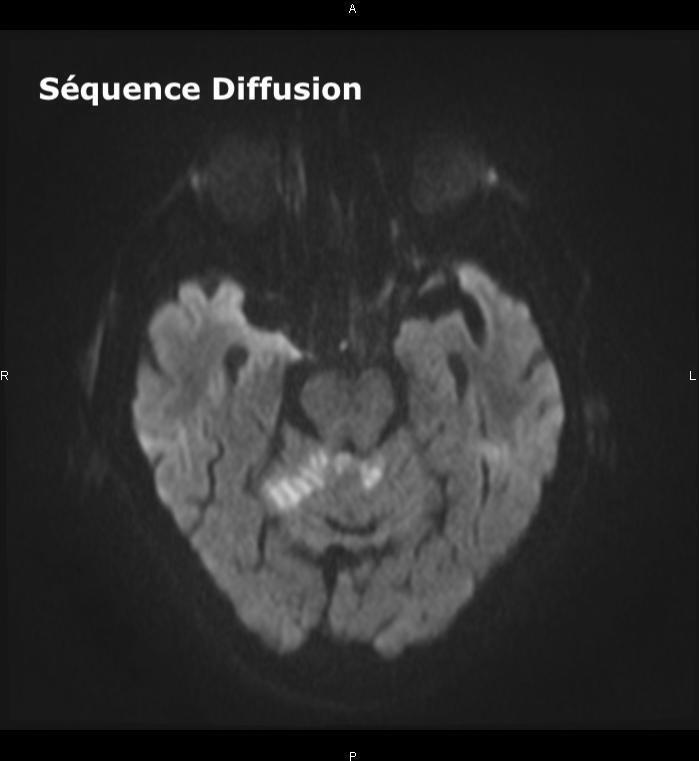

Un ou plusieurs déficits neurologiques (ataxie cérébelleuse, paralysie faciale) d’apparition soudaine (et le plus souvent d’emblée maximale), focale (tous les signes peuvent ici être expliqués par l’atteinte d’un seul territoire artériel) doivent faire évoquer le diagnostic d’AVC, et doivent conduire à une imagerie cérébrale rapidement.